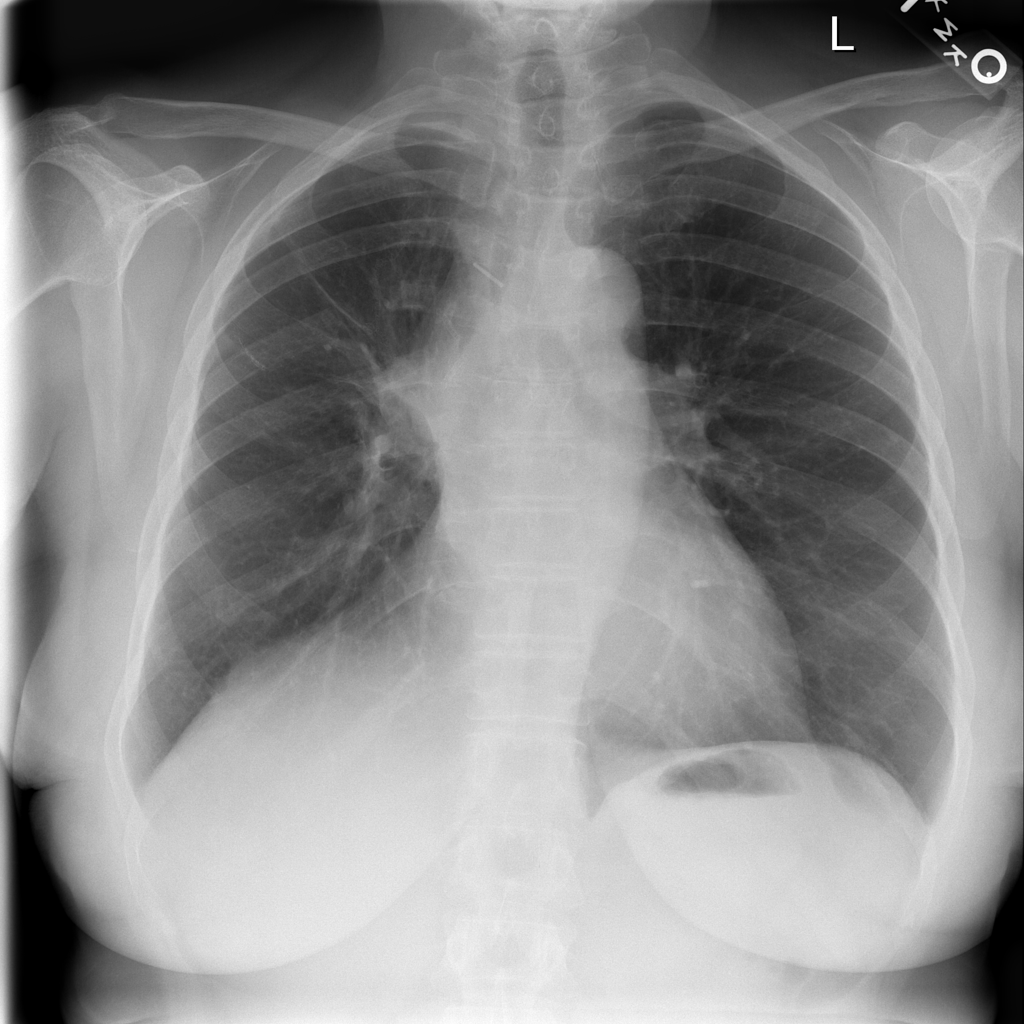

Mass

A mass is a larger focal opacity or lesion seen on the image. It is a descriptive finding that can have several causes and usually needs more imaging or clinical context to characterize.

PAT-C0E5 · IMG-001Mass

PAT-C0E5 · IMG-001

PA